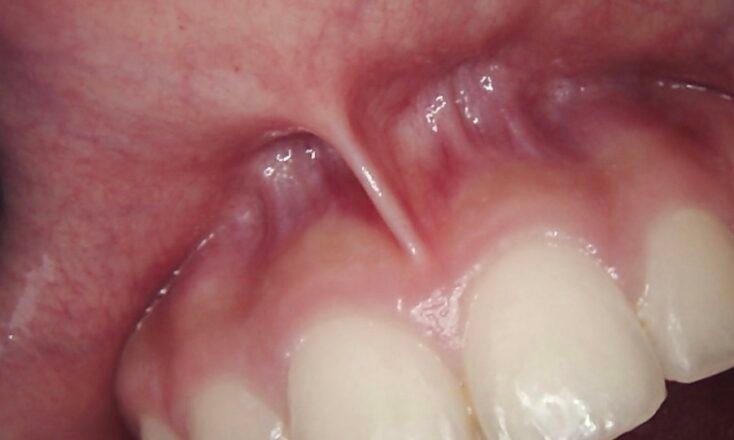

Correcting an Uneven Gum Line: If your gum tissue is asymmetrical, affecting your overall smile harmony.

Cosmetic Laser Gum Contouring: We reshape excess tissue to reveal more of your natural teeth, creating a balanced and symmetrical smile line.